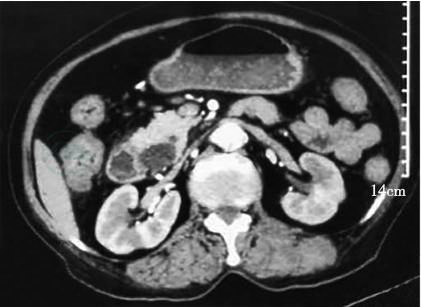

2020-03-15:当地医院腹部增强CT(图1~图3)示壶腹占位,大小约1.2cm×1.8cm,动脉期可见强化,肝内外胆管,胆总管及胰管扩张,胆总管最大内径约1.3cm,胰管最大径约0.5cm。当地医院血生化检查:白蛋白22g/L,总胆红素146μmol,直接胆红素102μmol。

图1 壶腹部占位

图2 胆总管扩张

图3 胰管扩张